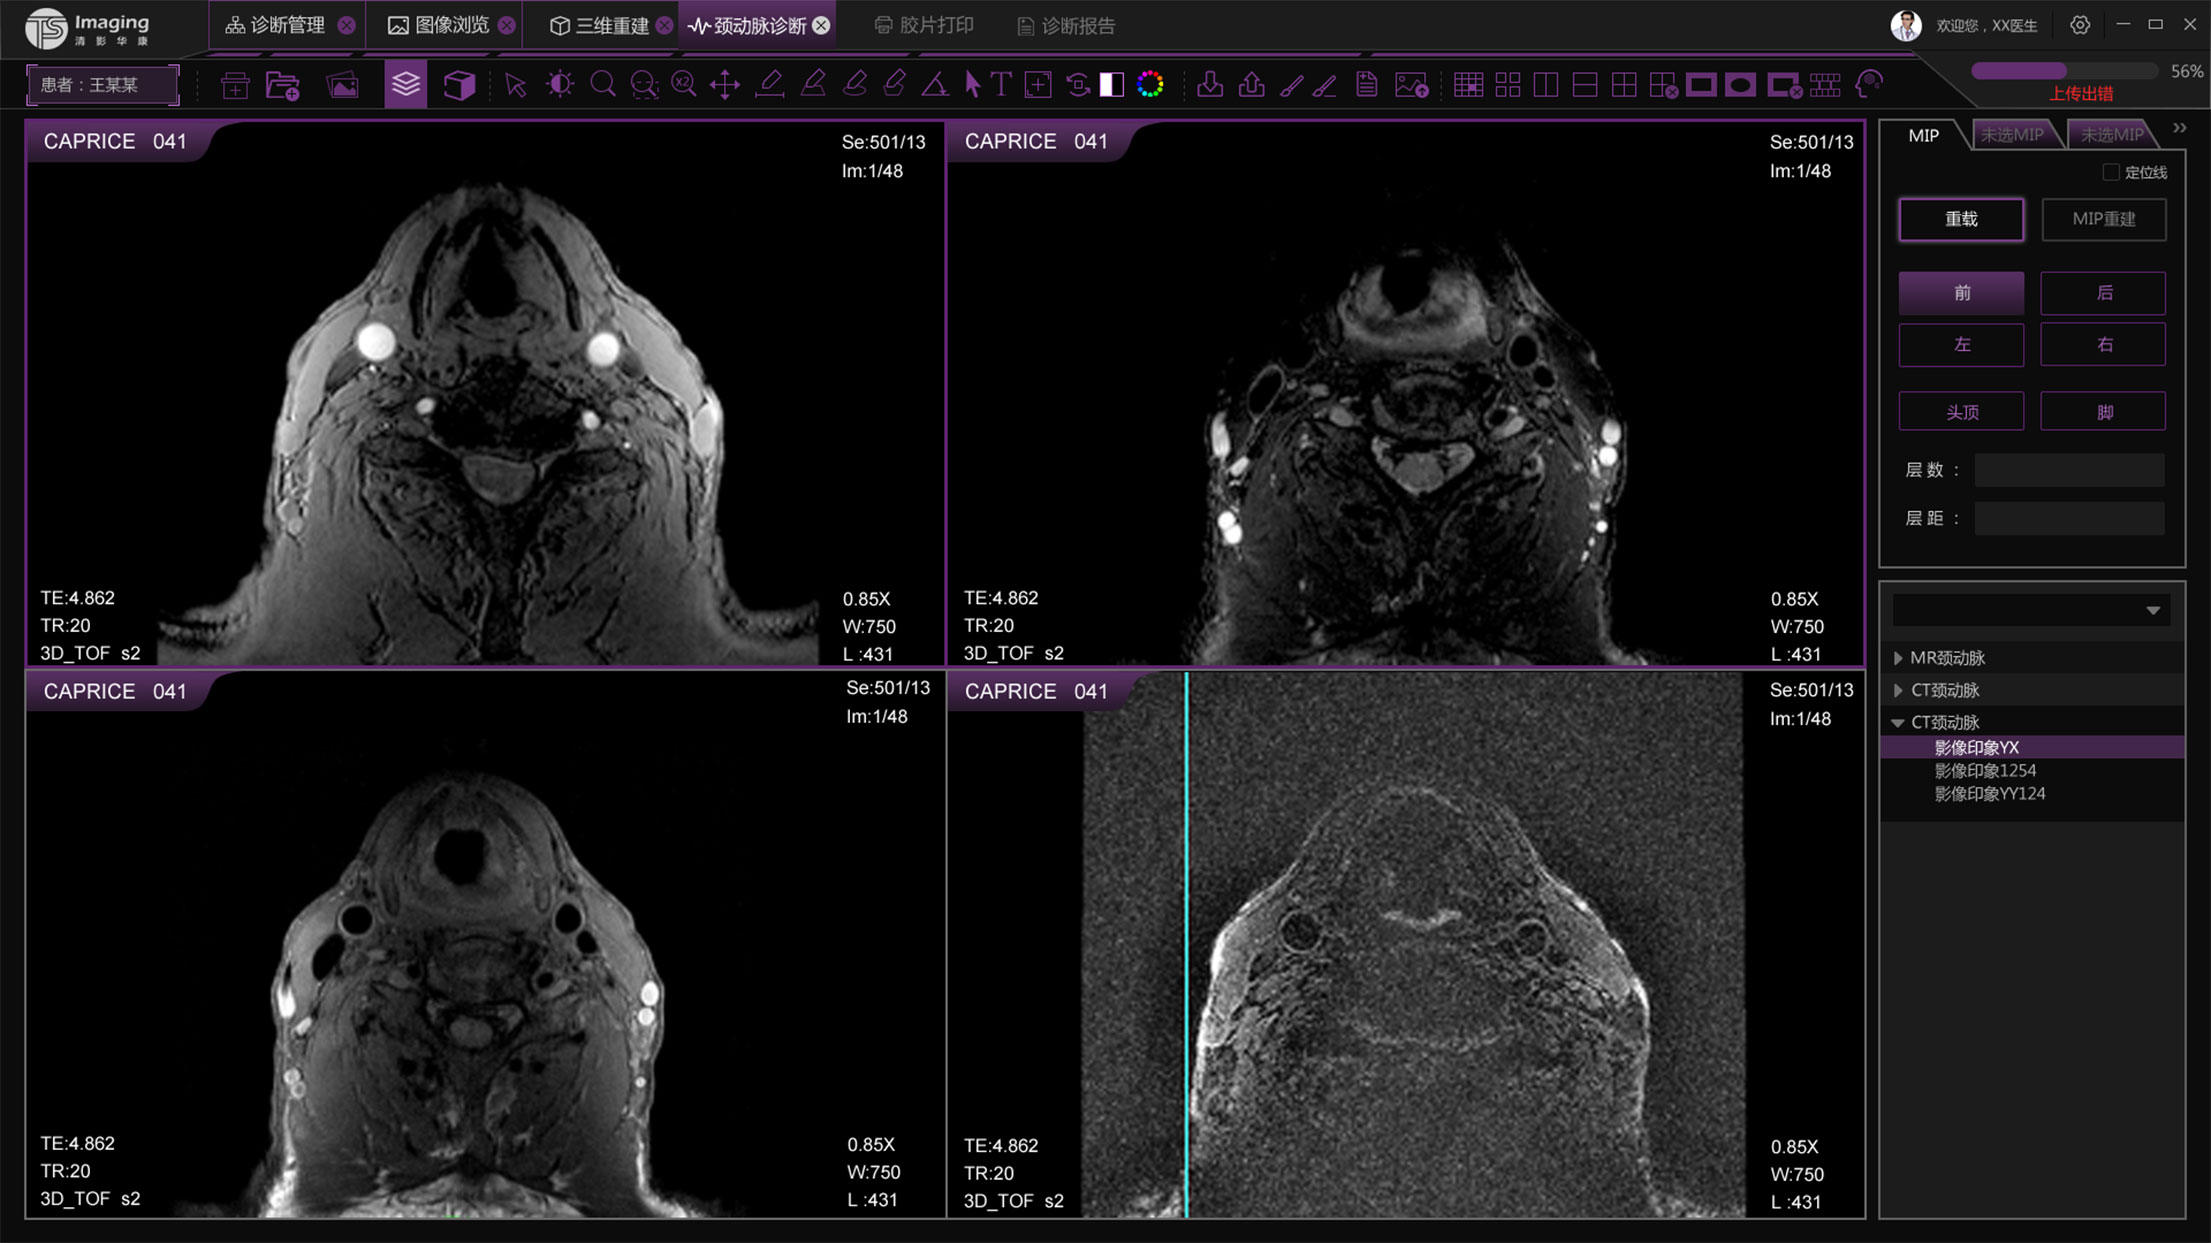

頸動(dòng)脈診斷頁(yè)面

頸動(dòng)脈診斷頁(yè)面整體布局和三維重建比較相似,最大的區(qū)別是右側(cè)的操作區(qū)域,血管分析都為按鍵操作,通過(guò)間隔的大小分成三部分。單層切片除了按鍵還有下拉菜單的操作。

頸動(dòng)脈診斷原型